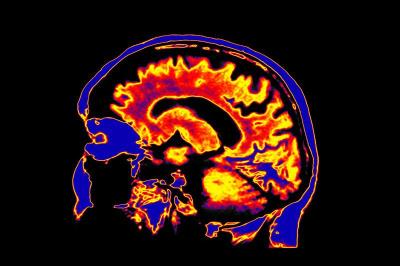

The application of single or multi-modality imaging for the spatio-temporal visualization of physiology and molecules including their function in biological and disease processes. Examples of the former may include analysis of receptors, metabolic changes, molecular motion, and blood flow. Example techniques include optical, nuclear medicine, MR, CT and ultrasound.

Imaging agents and radiotracers developed and approved for clinical use are used in MRI, PET, CT, Ultrasound and x-ray imaging. These can be used to diagnose disease as well as monitor treatment effects. The following lists include current and historical, modality-specific imaging agents and MI radiotracers for reference.